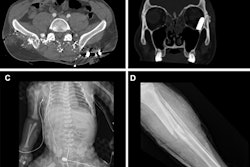

Ahmad's group developed a shortened "disaster" whole-body CT protocol as an alternative to conventional whole-body CT. The abbreviated protocol included axial CT head, axial CT angiogram vertex to pelvis, and sagittal reformat cervical spine. Four emergency radiologists read only these images from 10 whole-body CT complex trauma exams.

The readers identified 92% of acute traumatic findings; of these, 97% were identified by staff radiologists and 87% by fellows. There were some missed findings, but they were low grade and would not necessarily require immediate treatment in a mass-casualty event.